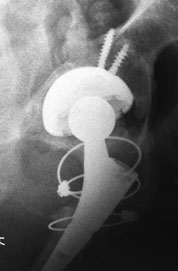

хотя на аксиальном видно, что чашка на винтах держится. Но болей быть не должно.

Впечатление о нестабильности серкляжа у меня не создается. Отметил зону, вызывающую сомнение

3. По нижней части чашки (изображение низкого качества) я вижу линию просветления - резорбция кости? Нестабильность чашки? Чашка сейчас держится в основном на винтах? Боли в паховой области через 4 года после ЭП можно объяснить этим.

4. Имеется бедренная ножка модульной конструкции - это не дефект ножки, а механический узел. Скорее всего это ножка переменной длины - привинчиваешь нижнюю часть подлиннее. Ревизионная? Ножка с переменной антеверсией???Видимо, на повторной операции, увидев расколотую проксимальную часть бедра и невозможность фиксации ножки здесь (что предпочтительнее), пошли на вариант длинная ножка с дистальной фиксацией (бесцементная? Не вижу цементной мантии, возможно она есть, но изображение низкого качества), а проксимальную часть бедра собрали на проволоку или тросы, с замками. Переход на дистальную (скорее всего бесцементную, что считаю ошибкой тактики хирургов) фиксацию ножки предопределил текущую картину. Перенос нагрузок с вертельной области почти в середину диафиза бедра привел к развитию стресс-шилдинга (хорошо видны на прямой проекции гипертрофированные кортикалы на уровне конца ножки), мне видится еще внедрение конца ножки в задний кортикал бедра и щель расшатывания на уровне дистальной трети ножки, могу ошибаться, разрешение низкое. Стресс-шилдинг, нестабильность, давление на кортикал - могут вызывать боли в бедре. Разгрузка проксимальной части закономерно привела к костной резорбции в зоне вертелов. Фиксации данной ножки там не было, нет и уже не будет.